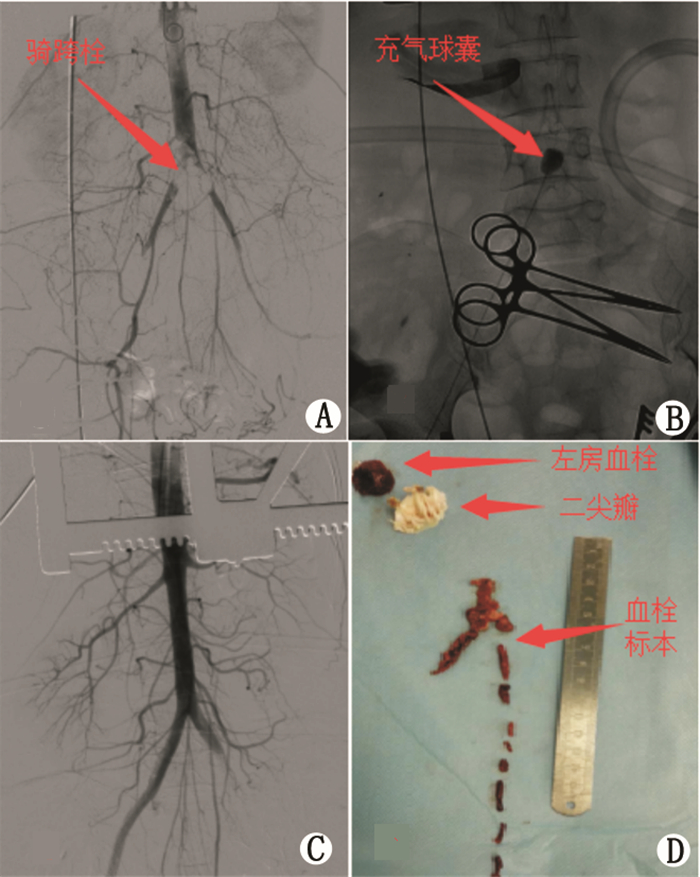

急诊于体外循环下行左心房血栓清除+左心耳结扎+二尖瓣置换+三尖瓣成形,同期行腹主动脉及下肢动脉取栓术。术中见左房明显扩大,切开探查发现左心耳内可见红色血栓,直径约2.5 cm类圆形,周围有数枚米粒样大小位于心耳内梳妆肌间隙中。二尖瓣瓣叶增厚、钙化,交界粘连消失,瓣下腱索增粗缩短,乳头肌融合,二尖瓣重度狭窄。三尖瓣瓣环扩张,注水实验显示大量反流。术中探查右侧股动脉搏动减弱,左侧股动脉搏动消失,右侧足背动脉(+),左侧足背动脉未及,左下肢自膝以下皮温降低,颜色苍白,左足趾颜色青紫。手术经过:全身麻醉,肝素化(肝素3 mg/kg体质量)后常规建立体外循环,清除左房血栓,缝扎左心耳。二尖瓣置入25#机械瓣(St Jude)1枚,三尖瓣置入30#MC3三尖瓣成形环,除颤后复跳。食道超声检查无殊后停体外循环,保持肝素化,保留主动脉插管及体外循环吸引功能。双侧腹股沟切口,游离股总动脉,股浅动脉,股深动脉套带备用。自升主动脉置入造影导管,造影见腹主动脉近髂动脉处鞍形充盈缺损(图 2A),左侧下肢见多处充盈缺损。阻断双侧股总动脉近远端,先从右侧切开股总动脉,向上插入5F的Forgarty导管,超过血栓进入腹主动脉下段后,充盈气囊向外拉(图 2B),取出大量混合血栓,反复取栓至无血栓拉出,开放阻断钳,近、远端均喷血良好,出血由体外循环吸引过滤后经主动脉插管回输体内。同样方法处理左侧。左侧股浅动脉向下置入4F的Forgarty导管,球囊导管配合通过闭塞段,取出较多红色血栓。同法置入股深动脉,未见血栓抽出。检查股深动脉返血良好,股浅动脉返血尚可,缝合切口。经主动脉、双侧髂动脉造影:下肢动脉显影均良好(图 2C),检查下肢动脉搏动良好,左足皮肤温度明显改善。拔除各插管,鱼精蛋白中和肝素,止血关胸。取出血栓标本,后病理回报:(腹主动脉及下肢动脉血栓)血栓组织伴机化,(左房血栓)混合性血栓,(二尖瓣)纤维瓣膜样组织伴黏液样变及玻璃样变性(图 2D)。

A:术中主动脉造影提示骑跨栓;B:球囊取栓;C:去栓后主动脉造影显示主动脉无充盈缺损;D:左房血栓、病变二尖瓣、骑跨栓及下肢血栓。 图 2 术中造影及标本